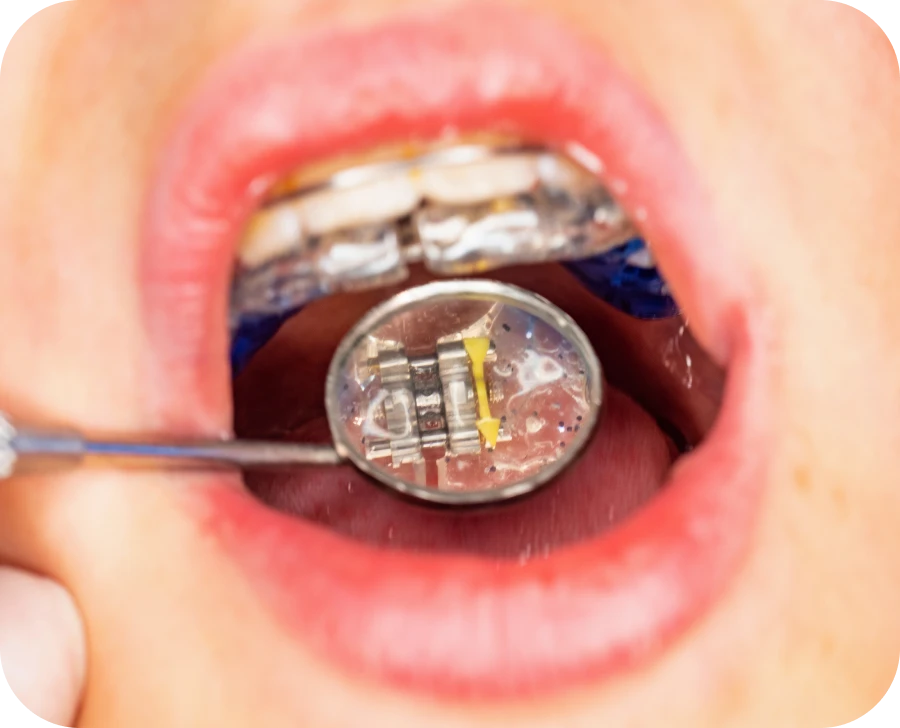

La plaque palatine repose sur le palais et applique une pression progressive. Cette action modifie la structure osseuse et guide la croissance du palais. Certains modèles possèdent une vis d’expansion qui permet des ajustements réguliers en fonction de l’évolution du traitement. L’activation progressive de cette vis permet d’exercer une force contrôlée sur la mâchoire afin de l’élargir sans provoquer de douleur excessive. Cet appareil favorise aussi une meilleure adaptation des dents en créant plus d’espace pour leur alignement optimal.

- Contrôles réguliers : le suivi permet d’ajuster la pression exercée par l’appareil pour assurer une correction efficace et progressive.